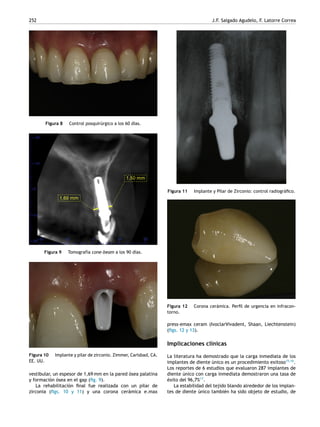

Figura 9 Tomografía cone-beam a los 90 días.

Figura 10 Implante y pilar de zirconio. Zimmer, Carlsbad, CA.

EE. UU.

vestibular, un espesor de 1,69 mm en la pared ósea palatina

y formación ósea en el gap (fig. 9).

La rehabilitación final fue realizada con un pilar de

zirconia (figs. 10 y 11) y una corona cerámica e.max

Figura 11 Implante y Pilar de Zirconio: control radiográfico.